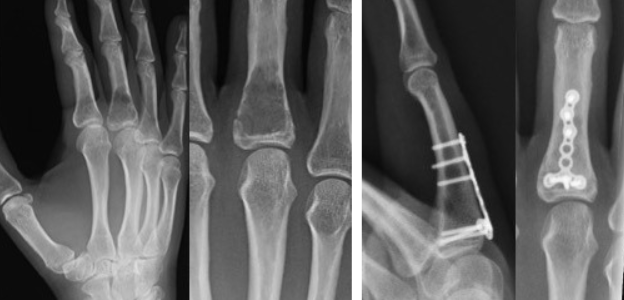

주로 X-ray(단순 방사선 검사)로 진단하며, 필요에 따라 CT, MRI 등 추가 영상 검사가 사용됩니다.

증상이 없고 우연히 발견된 경우, 반드시 치료가 필요한 것은 아니지만, 뼈가 약해져 있거나 골절이 있는 경우, 증상이 있을 경우 수술적 치료(뼈 속 연골 제거 및 이식)를 시행합니다.

뼈 이식은 자가골 또는 인공골을 사용할 수 있습니다.